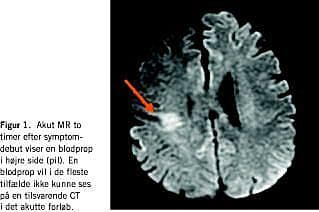

Der er flere mulige differentialdiagnoser til akut apopleksi (transitorisk cerebral iskæmi (TCI), migræne med aura, Todds parese eller pseudoapopleksi), som kun forløbet eller supplerende undersøgelser kan afsløre. Det største kliniske problem er dog, at debuttidspunktet for apopleksien ikke altid er let at fastlægge. Dette skyldes afasi, neglect eller bevidsthedsforstyrrelser hos den uobserverede patient, der lider af svær apopleksi og bliver fundet af arbejdskammerater eller pårørende, eller når apopleksien opstår under søvn. Nye magnetisk resonans (MR)-teknikker med diffusions- og perfusions-MR-skanning kan løse disse problemer, hvorved håbet er, at både effekten og sikkerheden under trombolysebehandling kan forbedres. Ved at benytte MR-teknikken (Figur 1) kan patienter udvælges på et patofysiologisk grundlag.

Ved obstruktion af et cerebralt kar går neuronerne centralt i området hurtigt til grunde, og der opstår et iskæmisk infarkt. Rundt om infarktet er der imidlertid hos de fleste patienter væv, som kun kan klare sig i en vis tid (fra timer til op til et døgn) via kollateral blodforsyning: den iskæmiske penumbra. Som tiden går, vokser infarktet ind i den iskæmiske penumbra. Symptomerne i den akutte fase stammer både fra selve infarktområdet og den iskæmiske penumbra, uden at det klinisk kan afgøres, om der stadig er væv, der kan reddes. Ved trombolysebehandling øges chancen for en hurtig opløsning af blodproppen og dermed en hurtigere reperfusion af det iskæmiske væv, hvorved der kan iagttages betydelig bedring af de neurologiske symptomer. Ved diffusions- og perfusions-MR-undersøgelse forud for trombolysebehandling kan det afgøres, hvor stort infarktet allerede er, og om der er en iskæmisk penumbra og dermed mulighed for at redde iskæmisk væv fra at gå til grunde.